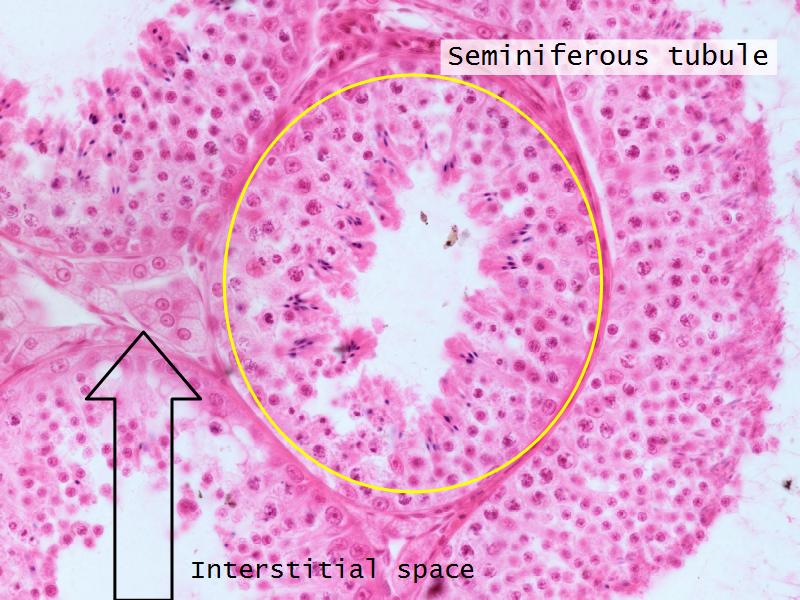

- Testis

- C2: Testis

- C2: Testis = testosterone

- D1: Leydig cells

- D1: Leydig cells = testosterone

- Slide 84: Testis